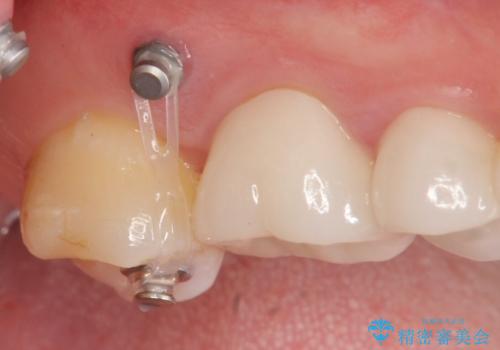

インプラントを埋入するのに十分な骨は存在しますが、放置した間に上の歯が伸びてきてしまいクラウンのスペース不足な状態です。

通常このような場合、神経を除去し歯を短くしたのちインプラント治療を行いますが、今回はマイクロインプラントを用いて歯を歯ぐきの方向へ沈めたのち神経を温存する形でインプラント補綴を行いました。